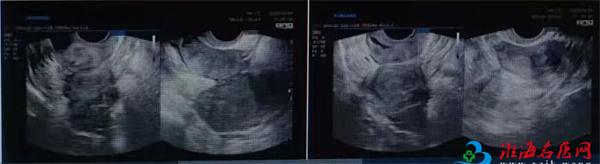

患者因“反复腹痛1年,逐渐加重”来我院妇科王海燕主任门诊寻求帮助。经详细检查发现:除左附件区存在直径约5厘米的囊性包块(内伴密集光点,提示巧克力囊肿可能)外,超声清晰显示患者为临床较为少见的“双子宫、双宫颈”畸形,且左侧子宫肌壁还探及一枚小肌瘤。这种先天性结构异常往往伴随更复杂的病理生理改变,大大增加了诊断和治疗的难度。